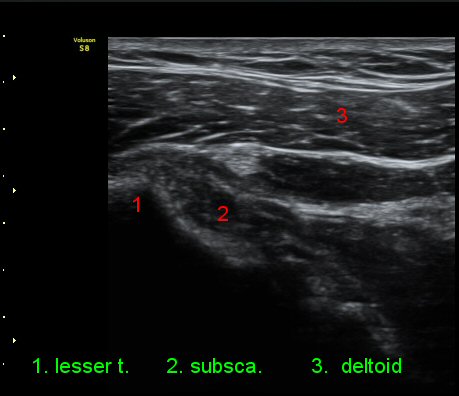

ÃÊÀ½ÆÄ °Ë»ç

2049205267_ba00cba1_IMG_20140331_2_3-c.jpg